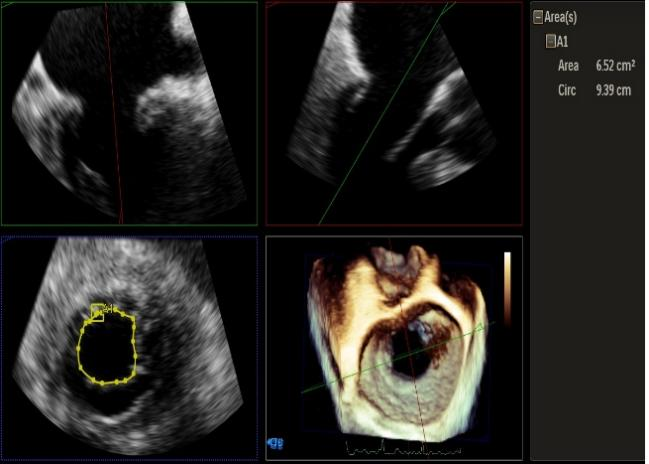

3D-color MV view:源自于交界区的大量反流

Qlab软件勾画估测瓣口面积约:6.52cm²